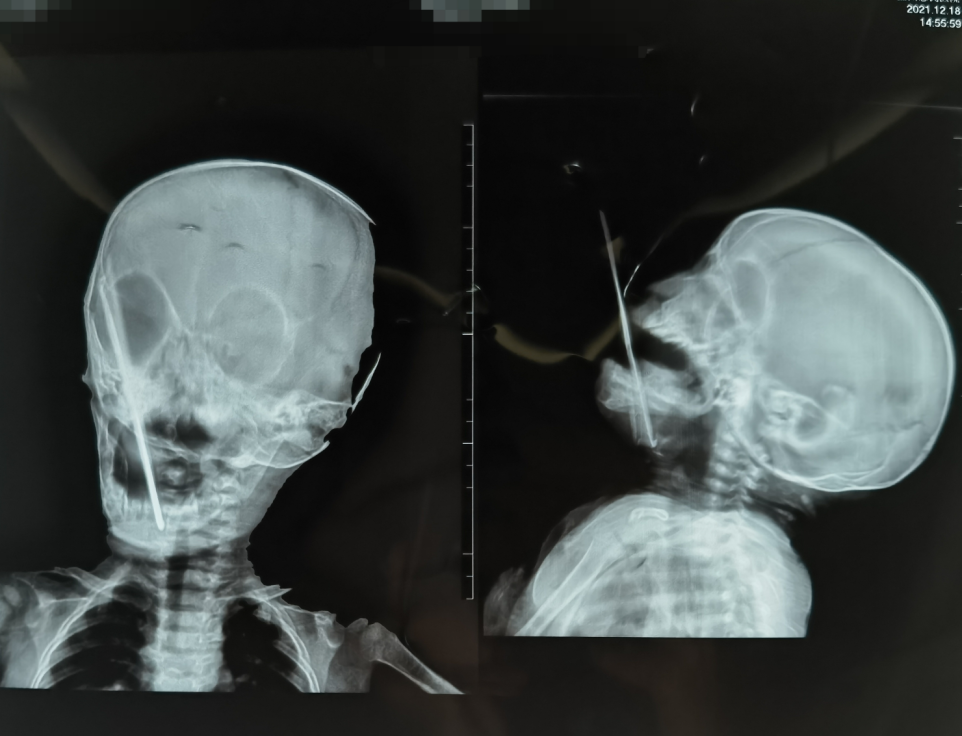

12月18日中午,年仅九个月大的某幼儿在贵州盘县家中玩耍时,无意间将一根长达16厘米的“钩针”刺穿口底。

家属紧急将患儿送至当地医院就诊,拍片后发现钩针插入口底较深,不具备处置能力,又立即被转送至曲靖,并继续辗转多家医院,因担心患儿太小、口底出血、肿胀随时出现生命危险,及缺乏专业的口腔颌面外科医生,患者家属连续遭到了4家医院的拒绝。

患儿家属抱着最后的希望到达昆明,托熟知的牙医紧急联系我院口腔颌面外科黎明主任,询问能否救治,黎主任明确表示没有问题,并联系患者入院就诊。此时已经距事故发生已经近十个小时。患儿因异物插入口底软组织中,非常痛苦,无法进食,精神萎靡,测血氧饱和度仅有85%。

口腔颌面外科团队在互联网上搜集钩针原图,了解钩针的构造和弯曲方向,发现插入口底的那部分恰好是钩针的最粗端。

麻醉成功后,由张长彬主治医师主刀,小心微创暴露钩针头部,顺利取出插入患者口底的异物,出血也得到妥善处置,目前,患儿状态恢复正常,正在积极消肿、抗感染治疗。

口腔颌面部血供丰富,涉及很多重要血管神经。患者异物位于口底,若处置不当,出血可导致口底肿胀,影响患儿的呼吸。此次异物为“钩针”,其头部有倒钩,在考虑其周围重要解剖结构的同时,还要避免钩针头部倒钩给周围组织带来的损伤,对医师是很高的考验。